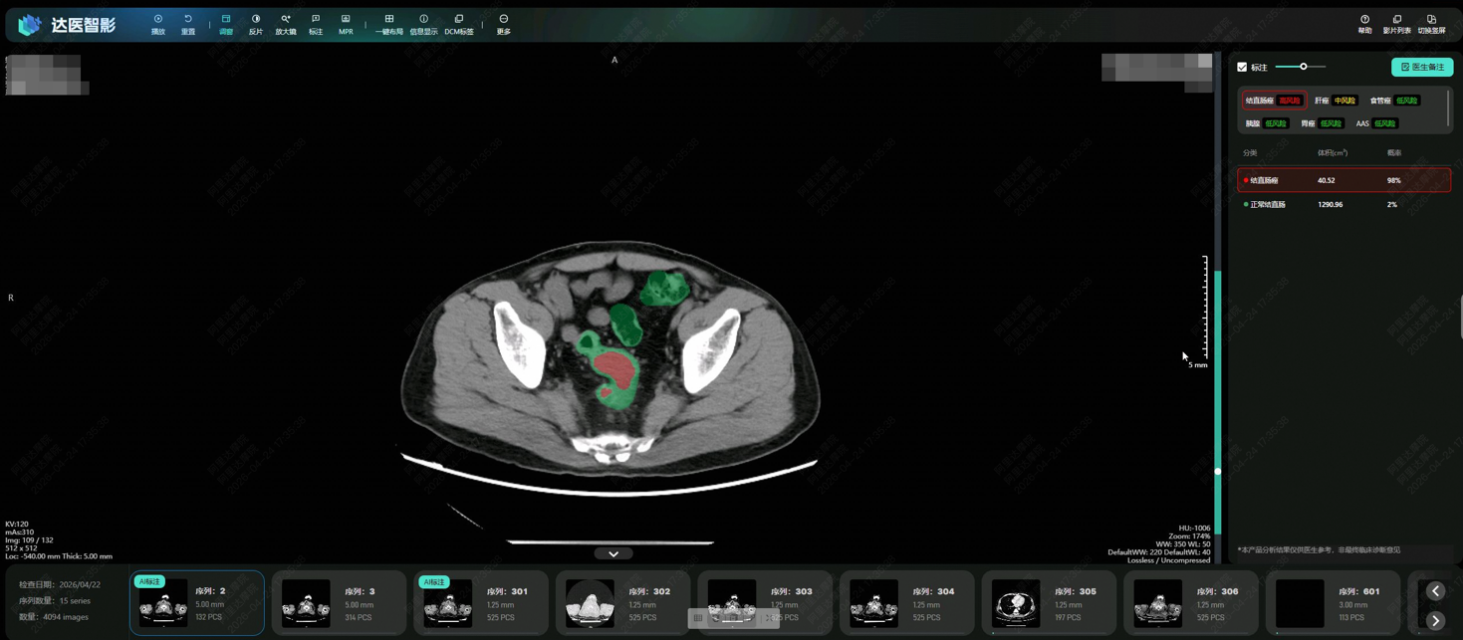

【环球网科技综合报道】4月28日消息,阿里巴巴达摩院联合广东省人民医院等机构研发出肠癌筛查AI模型DAMO COCA,从2.7万人的平扫CT影像中精准识别5例漏诊肠癌,敏感性、特异性分别达到86.6%和99.8%,在国际上首次提出了一种无需肠道准备、患者“无感”的肠癌机会性筛查方法。这也是继胰腺癌和胃癌之后,达摩院发布的第三个癌症筛查AI模型,意味着达摩院“平扫CT+AI”多癌筛查原创技术路线正式跑通。

为此,达摩院发挥在“平扫CT+AI”方面的多年技术积累,采用“先定位、后诊断”的两阶段深度学习架构和混合监督学习策略,更针对小于3厘米的早期肿瘤专门训练,使得AI模型能精细分割形态复杂的肠道部位并克服内容物干扰,检测可疑病灶。

研究团队发表在欧洲肿瘤内科学会官方期刊《肿瘤学年鉴》(Annals of Oncology,影响因子65.4)上的论文显示,六个男人躁到早上DAMO COCA模型的敏感性(即防止漏诊的能力)达到86.6%,特异性更达到99.8%,即误诊率仅有0.2%。与10名不同年资的影像科医生相比,DAMO COCA模型的敏感性显著高出20.4%,在乙状结肠、直肠等易漏部位上的表现尤为突出。而在AI辅助下,医生的敏感性和特异性可分别提高14.5%和3.1%,有效减少临床漏诊。

“肠道病灶在平扫CT影像上极易被遗漏,而DAMO COCA这样的AI工具能有效帮助医生解决这一痛点,赋能临床诊疗,也帮助更多患者在无需肠道准备的情况下机会性发现健康隐患”,广东省人民医院放射科主任刘再毅表示,“未来,需要把AI模型部署到更多地区和机构,通过大规模的前瞻性研究,进一步获得高质量循证证据。”